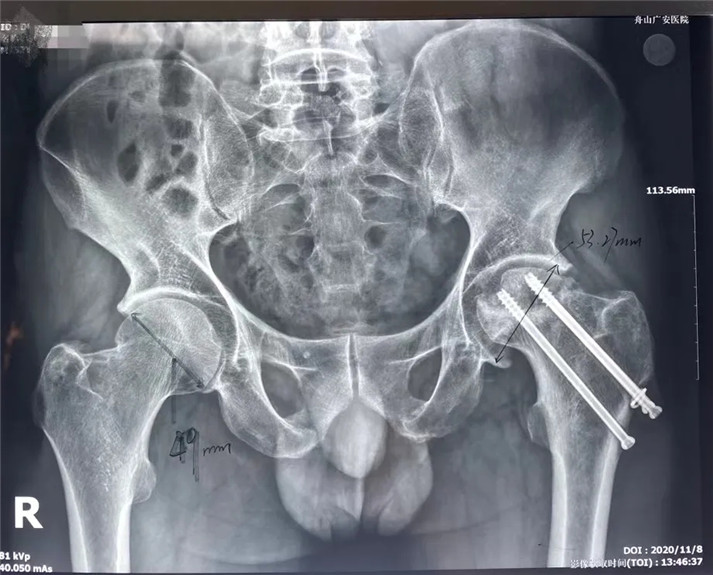

結合影像學表現(xiàn)研究后,骨科中心羅軍主任診斷丁先生為左股骨頭壞死,并建議其行全髖關節(jié)置換手術。

術前

考慮到患者的年齡、骨折類型等情況,以及患者的種種擔憂,為精準治療、加快愈合、避免關節(jié)脫位及肢體長短不等,羅軍主任團隊采用了近期引進的AI HIP置換術前規(guī)劃系統(tǒng)為患者行術前規(guī)劃。他們將丁先生的術前CT數(shù)據(jù)導入到系統(tǒng)中,通過自動識別骨盆和股骨建立了計算機數(shù)字三維模型。AI HIP顯示患者適合使用合適的髖臼杯、股骨柄、標準陶瓷球頭、陶瓷內(nèi)襯,并精準定位了截骨線,可以有效幫助醫(yī)生在手術中做到精確截骨。

AI HIP術前規(guī)劃